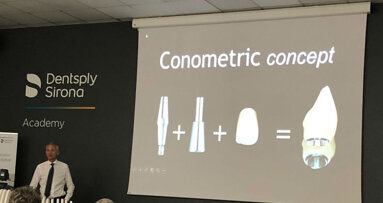

L’8 novembre si è tenuto presso la Dentsply Sirona Academy di Verona il Peers Closed Meeting riservato ai membri Peers, clinici esperti ed appassionati ...